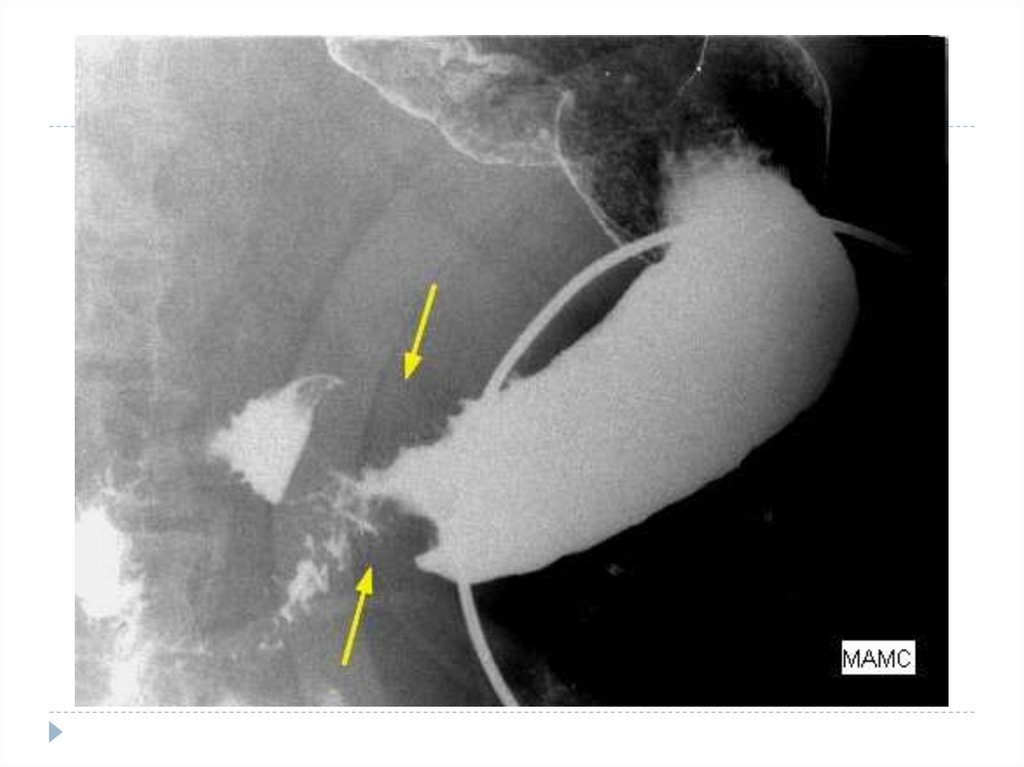

фиброэзофагогастродуоденоскопия (позволяет увидеть дефект

слизистой, определить его размеры и характер, взять кусочек

ткани для гистологического исследования);

рентгеноскопическое исследование пищевода и желудка с

контрастированием.